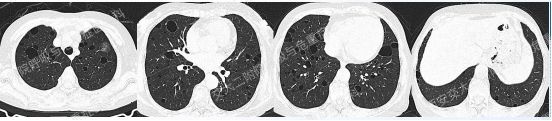

第一期埋下的伏笔,以下2例不同患者的胸部影像改变,又分别考虑什么疾病呢?答案呼之欲出,相信大家也越来越清晰了!